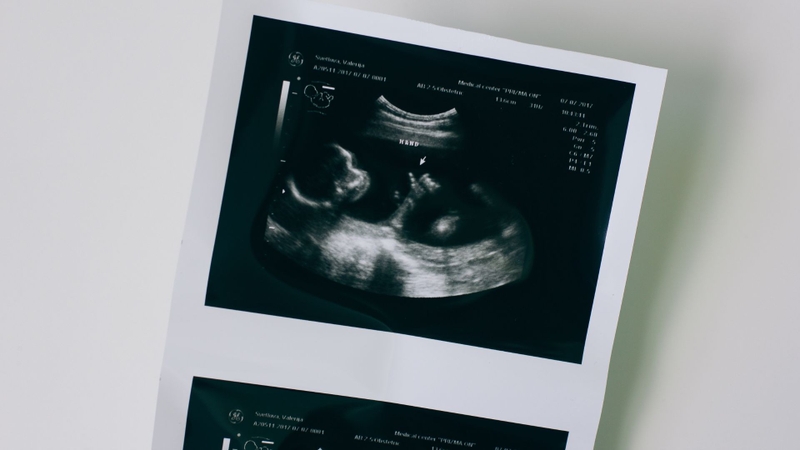

Thai nhi phát triển từng ngày trong bụng mẹ, kéo theo đó là sự thay đổi liên tục của các chỉ số sinh học. Trong đó, đường kính lưỡng đỉnh là số đo mặt cắt ngang hộp sọ của thai nhi, được đo qua siêu âm, tính từ xương thái dương bên này đến xương thái dương bên kia. Đường kính lưỡng đỉnh có mối liên hệ mật thiết với sự phát triển của não bộ, bởi nó phản ánh kích thước hộp sọ, nơi chứa đựng và bảo vệ cơ quan quan trọng này.

Việc theo dõi chỉ số này giúp bác sĩ đánh giá sự phát triển của thai nhi có tương xứng với tuổi thai hay không. Thông qua siêu âm, bác sĩ sẽ tiến hành đo đạc cẩn thận và ghi nhận lại chỉ số này trong sổ khám thai. Mẹ bầu cần lưu ý rằng, đường kính lưỡng đỉnh chỉ là một trong nhiều chỉ số quan trọng, bên cạnh chu vi vòng bụng thai nhi, chiều dài xương đùi và các số đo khác. Tất cả những chỉ số này kết hợp lại mới cho bức tranh toàn diện về sự phát triển của thai nhi.